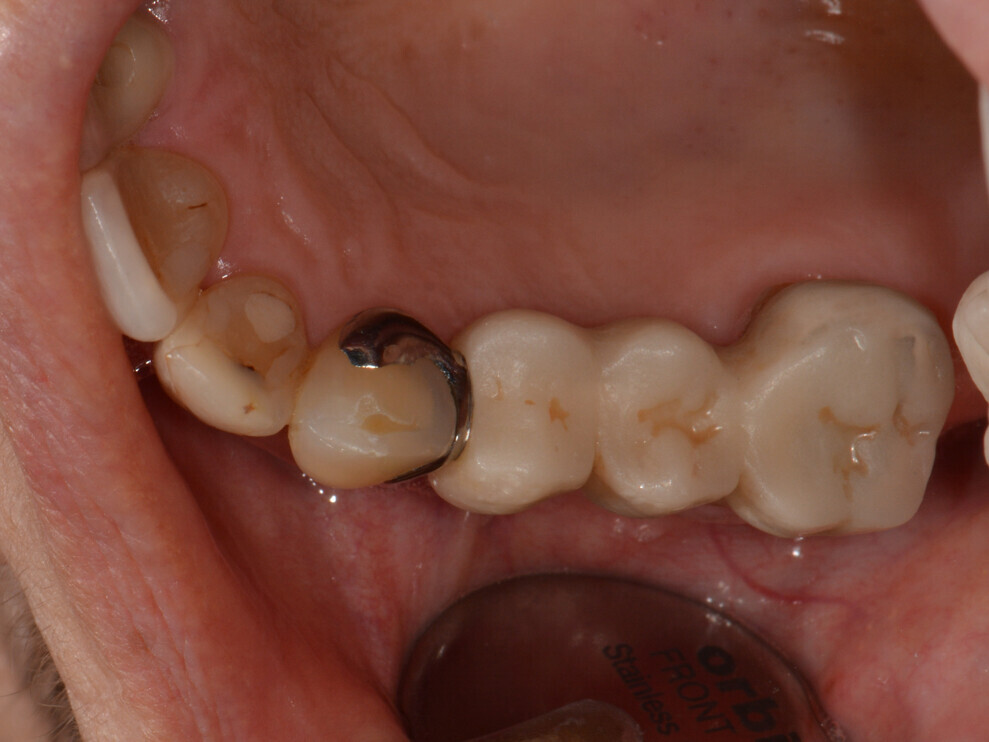

The provisional bridge was modified at the base to create space in case of swelling and inserted with methacrylate-based temporary luting material (Bifix Temp, VOCO). The screw-retained final restorations were fabricated from a multilayered monolithic zirconia (DD cubeX2 ML, Dental Direkt; Fig. 14).

Fig. 14: Screw-retained final restorations.